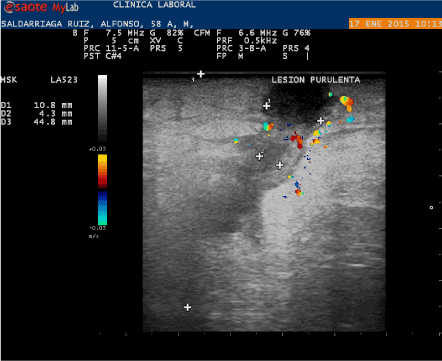

The fistula was treated once a week for 8 weeks. The healing was monitored by a sonogram. With the skin now closed, using a contrast dye was not practical. Initially secretion from the fistula was about 50 cc every four to five days and as the treatment began the outflow reduced until the wound completely healed. The patient had been advised to have major surgery involving a hemicolectomy and a likely colostomy with closure of the second colon.

Figure 3: Ecografia De Fistula Ecografia Post Tratamiento